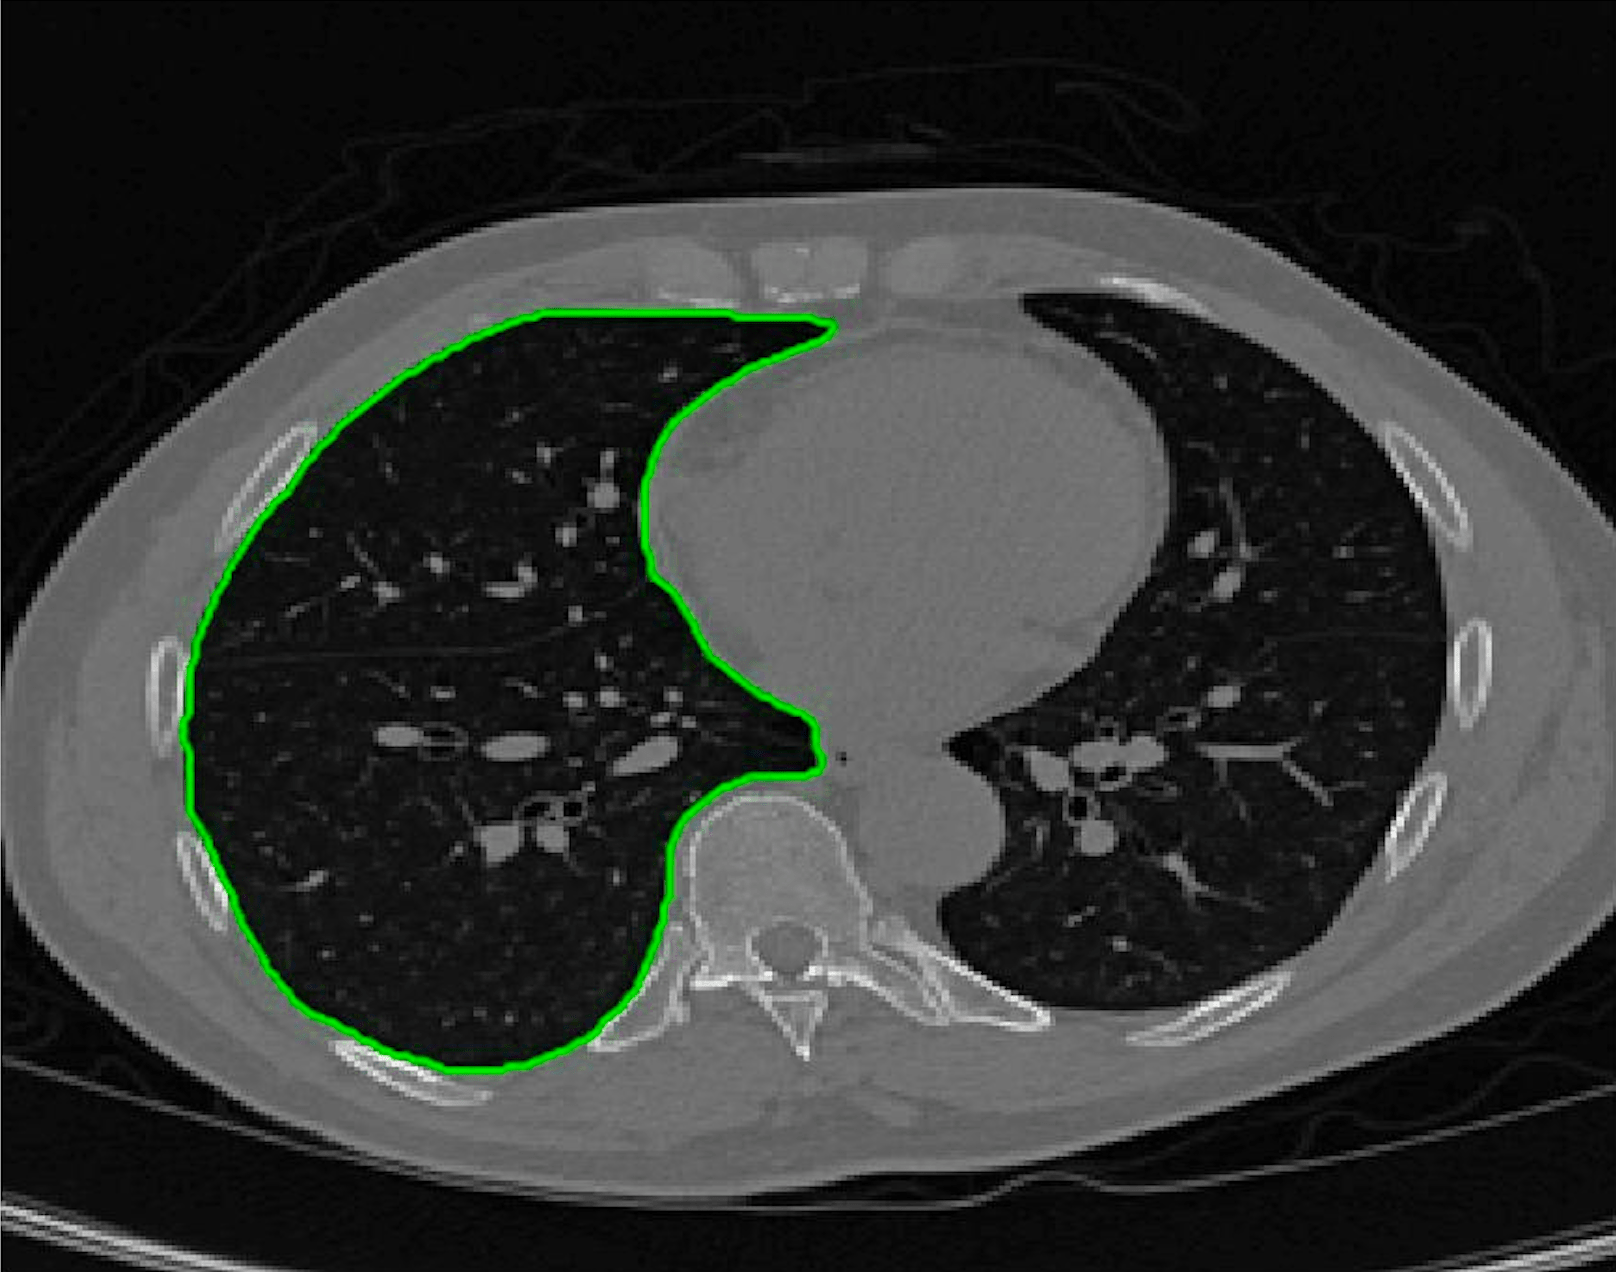

Test Images. We will perform initial tests on the images shown in Figs. 5–7. We have provided the ground truth and initialisation used for each image. Test Images 1–3 are synthetic, Test Image 4 is an MRI scan of a knee, Test Images 5–6 are abdominal CT scans, and Test Images 7–9 are lung CT scans. They have been selected to present challenges relevant to the discussion in §2. We focus on medical images as this is the application of most interest to our work. In the following we will discuss the results in terms of synthetic images (1–3) and real images (4–9). We also test the proposed approach on a larger data set of 30 CT images (a sample of which is presented in Fig. 18), comparing against existing selective methods detailed in §3.

Real Images. In Fig 12 we present results for Test Images 4–6. Here, the proposed model performs in a similar way to its competitors because these images are more typical selective segmentation problems in the sense that there is a clear distinction between the foreground and background intensities. In particular, the values in each case are: Test Image 4 , Test Image 5 , and Test Image 6 . It can be seen that the proposed model is competitive compared to previous approaches. The performance is quite poor for Test Image 5, but is arguably still the best for this challenging case. In Fig. 13 we present results for Test Images 7–9. Here the proposed model outperforms previous approaches significantly for each image. This is mainly due to the type of image considered. Specifically, the true intensities are: Test Image 7 , Test Image 8 , and Test Image 9 . The proposed model is capable of achieving results where , with other models failing completely in these cases.

Real Images. In Table 1 we can see that the proposed model is the most successful in terms of optimal accuracy. It is worth noting some inconsistency in the other models, with all but GAV having results that fall below TC for at least one image. GAV performs well for Test Images 4–9, with the proposed model slightly outperforming it in each case. It is worth reminding the reader that for GAV the parameters have been refined for each example. Fixing this results in more variability in the quality of results. The proposed model has no such parameter optimisation between examples. CAC and SRW perform reasonably well for these images, although are sometimes substandard for Test Images 4-7. This is despite extensive refinement of the user input to achieve an acceptable result. We present the optimal results for Test Image 9 in Fig. 14. Here we can see how much variation there is in the quality of results for this lung CT image. CAC and SRW are competitive in this instance. Of the remaining approaches GAV is the most competitive (TC ), but is visually inadequate. Two other models (CV, HYB) fail completely. In this case, the problem looks quite straightforward and yet other fitting terms are insufficient to produce a good result. Again, the proposed model tends to be superior in cases where and is capable of achieving very good results for all the images considered. This highlight the advantages of the proposed fitting term.

Real Images. In all cases for Test Images 4–9 the mean values show that the segmentation results are highly accurate. Also, we notice that the variances are very reasonable demonstrating the robustness of varying the user input. This is an important aspect of selective segmentation, and highlights the advantages of the proposed fitting term. For Test Images 4–6 we observe more variability in the accuracy due to minor intensity inhomogeneity in the foreground. This means randomising the user input will be more sensitive. However, we can see that the results are very good with the mean accuracy being competitive with the optimal accuracy of comparable methods. In the case of the lung CT images (Test Images 7–9) the variance in TC values is very small, due to the homogeneity of the foreground. Again, it is important to compare the results of random results using our proposed model to the optimal result of comparable methods. For these images all of the methods (except GAV,CAC, and SRW) have at least one TC value below 0.9. However, GAV requires the tuning of additional parameters whilst the proposed model does not. The results for CAC and SRW also rely on extensive requirements of the user input to achieve this accuracy, whereas random input compares favourably here. Compared to GAV, we can see that the mean of our tests is similar to the optimal value of GAV. One exception is for Test Image 9 (shown in Fig. 14), where there is a significant gap in favour of our model. Again, from Fig. 16, we can see that the worst result of randomising the user input for the proposed model is competitive with the optimal results of the alternatives. This is one of the most encouraging aspects of the tests; the proposed model is remarkably robust to varying user input. This proves that successful results with minimal, intuitive user input is possible for a range of examples.